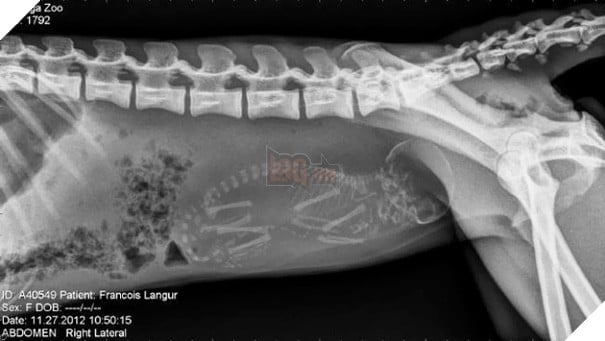

Hình ảnh trông kỳ lạ và cực khó đoán như thể một con vật 4 chân nào đó mang thai em bé. Tuy nhiên, đây là ảnh chụp X-quang một con voọc đen má trắng (khỉ Francois) mang thai.